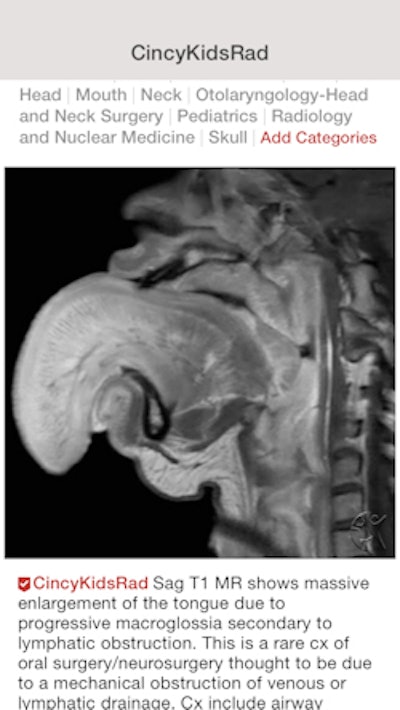

Figure 1 allows physicians to upload deidentified images and photos of cases and get feedback and opinions from other users. Because cases are constantly uploaded, users can learn on an ongoing basis.

Groups can also set up accounts on Figure 1; one of the most popular radiology groups is run by the department of radiology and medical imaging at Cincinnati Children's Hospital and provides pediatric radiology education.